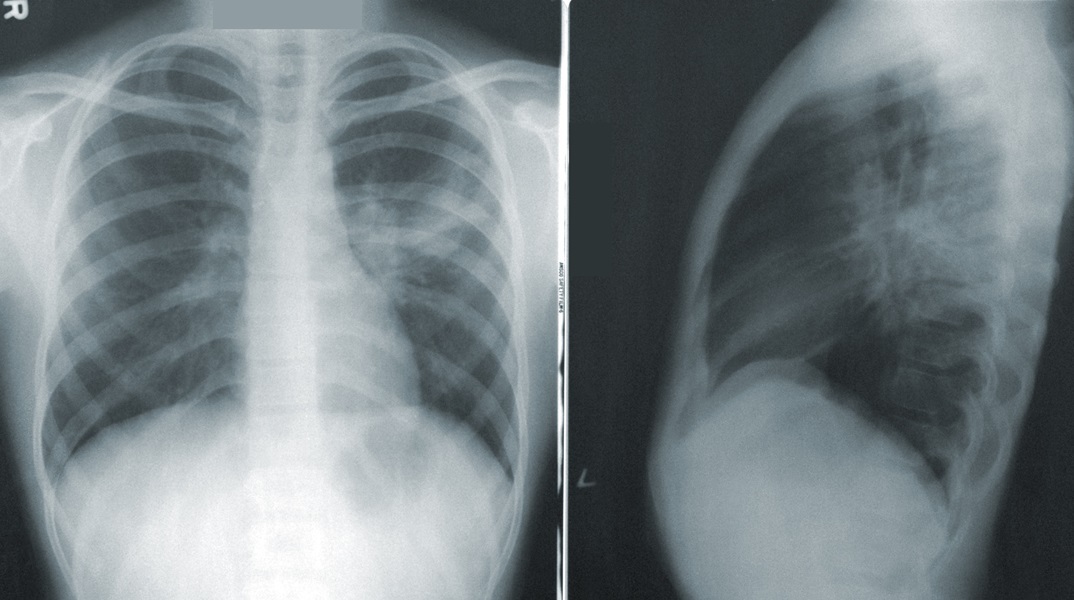

Όπως τόνισε ο κ. Μαγιορκίνης η αποκαλούμενη και περιπατητική πνευμονία έχει αρκετά ήπια συμπτώματα και εμφανίζεται απλά με πυρετό, ωστόσο η ακτινογραφία όπως είπε δείχνει ότι ο πνεύμονας έχει δημιουργήσει πνευμονικά οζίδια.